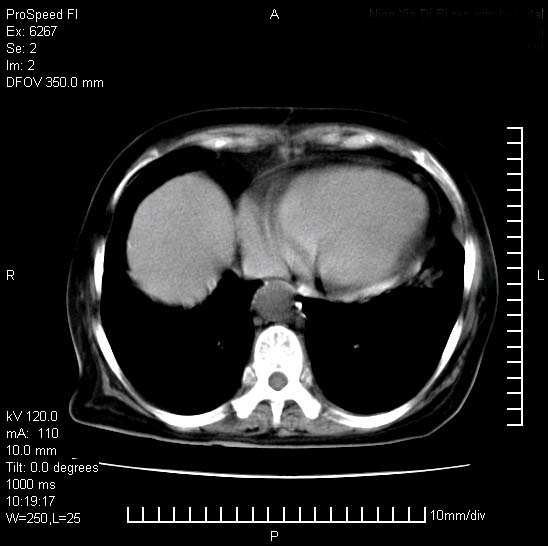

患者糖尿病,腹痛,恶心,呕吐。黄疸,意识较差,血糖很低(数值不详),临床以胆囊,胆管炎,低血糖反应收治。看的腹片少,各位帮忙看看,胰腺有问题吗??

1.胰腺体积增大,胰周脂肪间隙消失,胰腺炎可以确定。必要时实验室进一步检查。

胰腺体积增大,胰周脂肪间隙消失,考虑胰腺炎。胆囊炎,胆石症。

脾大,原因?胆结石;胰腺肿大,边缘模糊,建议查定性指标血尿淀粉酶,除外胰腺炎

1)考虑胰腺炎;建议查血尿淀粉酶。2)胆囊炎,胆囊结石。3)脾大。